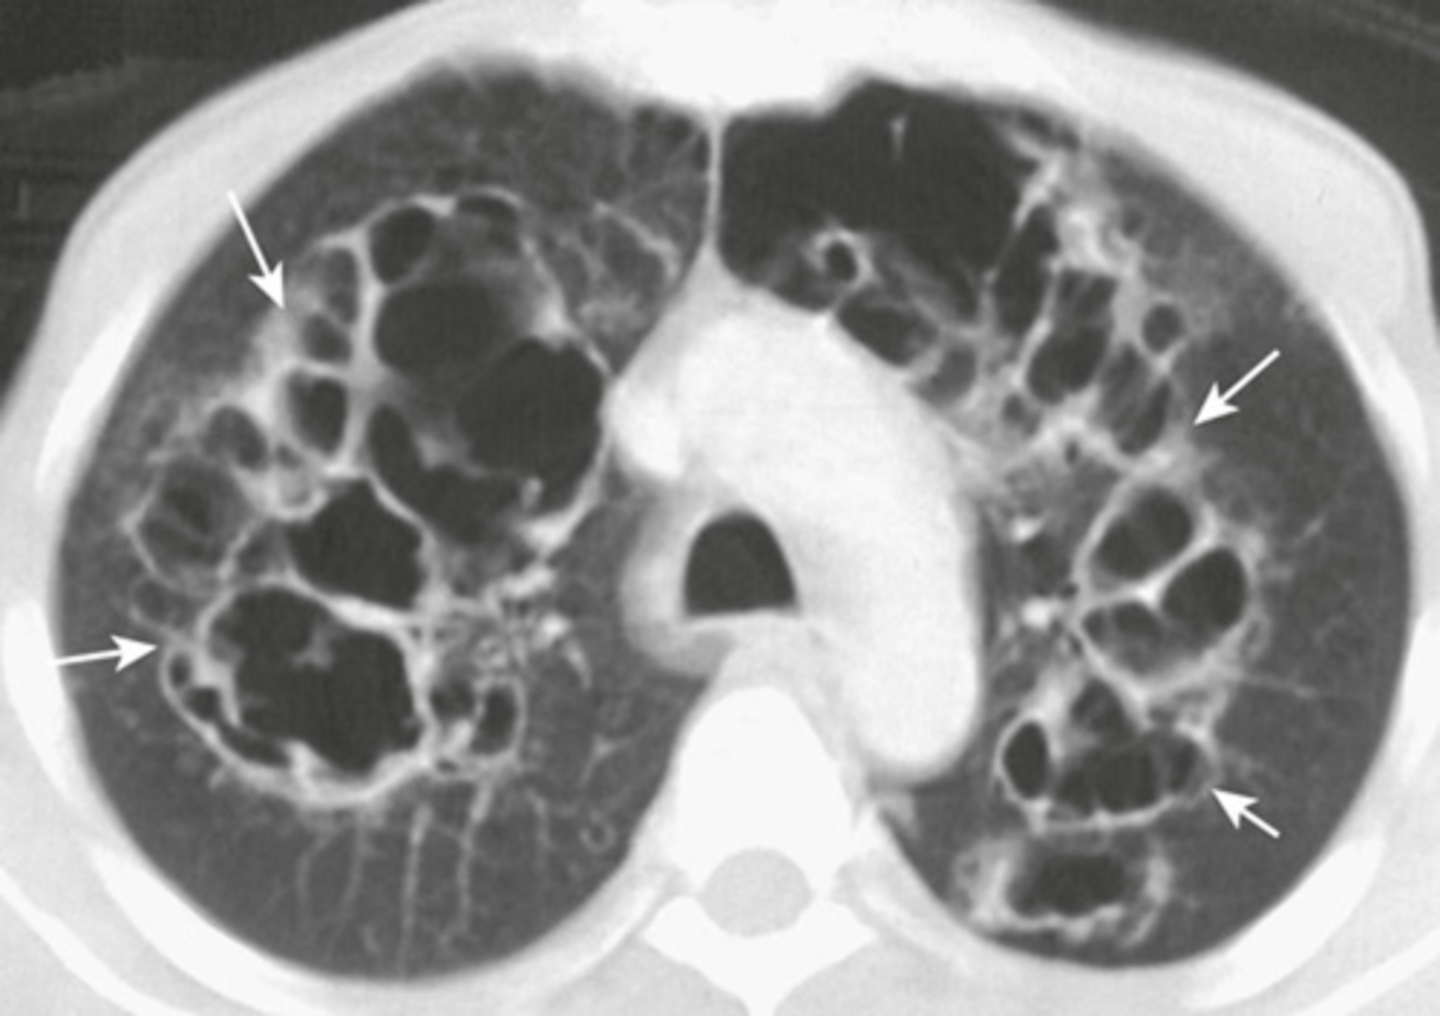

-parallel line opacities (tram tracks)

-signet ring signs

-thickened walls of dilated bronchi

-cystic lesions

bronchiectasis appearance